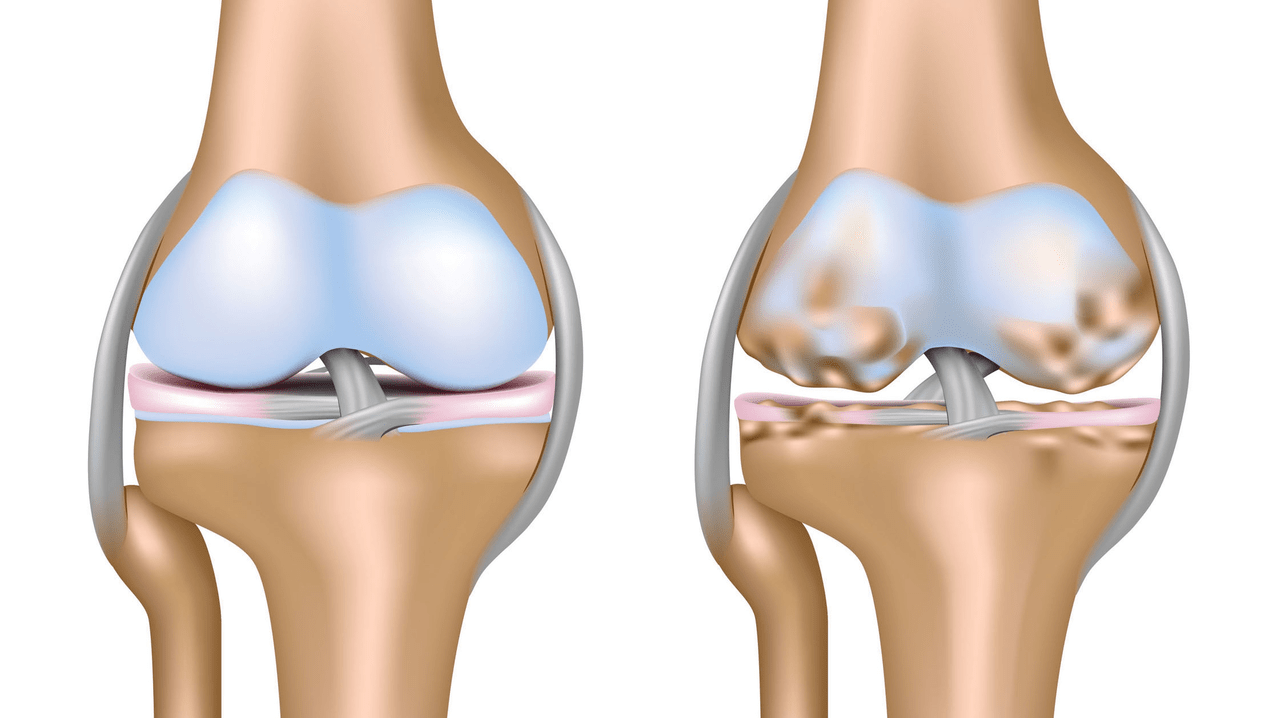

Kelio sąnario artrozė (gonartrozė) yra progresuojanti lėtinė kelio sąnarių liga, pasireiškianti jo kremzlinės dalies (šlaunikaulio ir blauzdikaulio sąnarinių paviršių) pažeidimu, suplonėjimu ir sunaikinimu, taip pat subchondralinio kaulo pažeidimu. Tyrimais (artroskopija ir magnetinio rezonanso tomografija) įrodyta, kad procese, be sąnario kremzlės pažeidimo, dalyvauja meniskai ir sinovinė membrana. Gonartrozė yra viena iš labiausiai paplitusių ortopedinių patologijų. Yra jos sinonimai – osteoartritas (OA), deformuojantis artrozė. Liga yra svarbi socialinė-ekonominė problema, nes yra plačiai paplitusi ir dėl nuolatinio skausmo smarkiai pablogina pacientų gyvenimo kokybę, be to, tampa didelės neįgalumo priežastimi.

Iki praėjusio amžiaus aštuntojo dešimtmečio vidurio nebuvo vieningo ligos apibrėžimo. Tik 1995 m. Amerikos reumatologijos koledžo osteoartrito komitetas šią ligą apibūdino kaip mechaninių ir biologinių veiksnių, dėl kurių sutrinka sąnario kremzlės ekstraląstelinės matricos skilimo ir sintezės procesai, rezultatas. Dėl to skaidulų irimas ir degeneracija, formuojasi įtrūkimai, osteosklerozė ir subchondrinio kaulo žievės sluoksnio tankinimas, auga osteofitai, formuojasi subchondralinės cistos.

Sergant artroze (osteoartroze), be laipsniško kremzlės irimo, jos elastingumo ir amortizacinių savybių nykimo, į procesą palaipsniui įsitraukia kaulai. Esant apkrovai, atsiranda aštrių briaunų (egzostozės), kurios klaidingai laikomos „druskų nuosėdomis“ - esant klasikinei artrozei, druskos nenusėda. Progresuojant artrozei, ji toliau „valgo“ kremzlę. Tada kaulas deformuojasi, jame susidaro cistos, pažeidžiamos visos sąnario struktūros, sulinksta koja.

Antrame etape kremzlės sluoksnis smarkiai plonėja, o kai kuriose vietose jo visiškai nėra. Išilgai sąnarinių paviršių kraštų atsiranda osteofitai. Keičiasi sąnario sinovinio skysčio kokybinės ir kiekybinės savybės – jis tampa tirštesnis, klampesnis, dėl to pablogėja jo maistinės ir tepimo savybės. Skausmas būna ilgesnis ir intensyvesnis, judant dažnai pasigirsta traškėjimas. Yra nedidelis arba vidutinis judėjimo apribojimas ir nedidelė sąnario deformacija. Analgetikų vartojimas padeda sumažinti skausmą.

Gonartrozė, III stadija

Kremzlės trūkumas daugumoje pažeistų vietų, sunki kaulo sklerozė (sukietėjimas), daug osteofitų ir staigus sąnario tarpo susiaurėjimas arba nebuvimas. Skausmas beveik nuolatinis, eisena sutrikusi. Judrumas smarkiai apribotas, pastebima sąnario deformacija. NVNU, fizioterapija ir kiti standartiniai kelio artrozės gydymo metodai yra neveiksmingi.